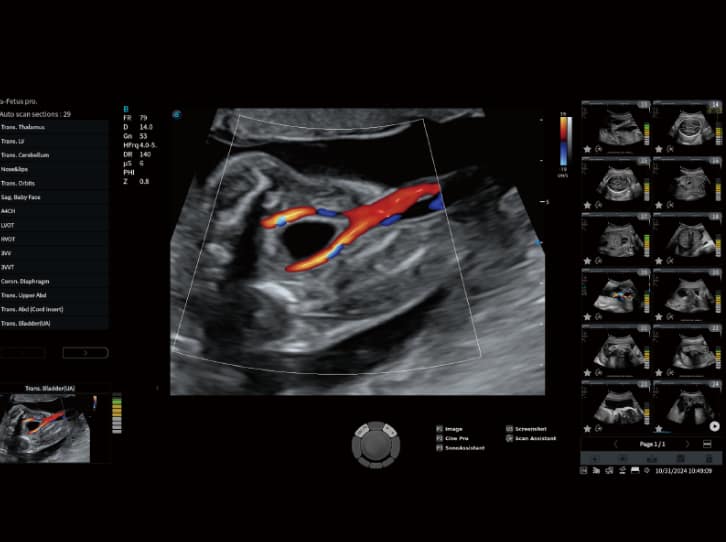

• S-Fetus: Eine One-Stop-Lösung, die mit nur einem Klick 29 Standardebenen des Fötus identifiziert und 13 biometrische Messungen automatisch durchführt.

• Spezialisierte Diagnostik: Mit Tools wie HyCoSy zur Prüfung der Eileiterdurchgängigkeit, S-ERA zur Volumenquantifizierung des Endometriums und S-PF zur Beurteilung des Beckenbodens bietet das Fenix-Modell ein lückenloses Paket für die Gynäkologie.